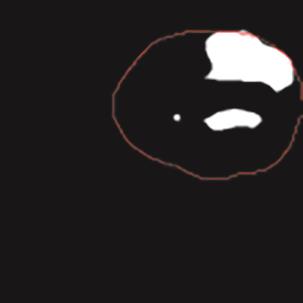

乳腺癌是全球女性最常见的恶性肿瘤之一,准确的病变分割对于乳腺癌的早期诊断与治疗具有重要意义。然而,由于病变形态的多样性以及超声成像机制的复杂性,现有基于深度学习的乳腺超声图像病变分割方法在分割准确性方面仍面临巨大挑战。为进一步提升乳腺超声图像中病变区域的分割精度,该文基于经典U-Net架构,提出了一种新型乳腺超声图像病变分割网络(CWSASKM-BBAM-Net)。首先,在网络中引入逐通道空间自适应选择核卷积模块(CWSASKM),根据不同通道的语义特征为每个空间位置自适应选择感受野大小,以增强多尺度信息的建模能力;然后,引入双向边界感知机制(BBAM),通过融合正向与反向注意力,对目标显著区域及其边界进行协同建模,同时逐步提升对非显著区域与病变区域的区分能力,以进一步强化边界信息的表达;最后,在3组公开乳腺超声图像数据集(BUSI、UDIAT和STU)上开展分割实验。结果表明:该方法在数据集BUSI上的杰卡德指数、精确率、召回率和Dice相似系数分别为71.97%、82.85%、81.40%和80.44%,较次优方法分别提升1.69、1.05、1.28和1.84个百分点;在数据集UDIAT上,这4项指标分别达到78.14%、88.31%、86.73%和86.10%,较次优方法分别提升了2.75、2.04、0.56和2.01个百分点;在外部数据集STU上,该方法也取得了优于其他方法的整体表现。实验结果表明,CWSASKM-BBAM-Net在乳腺超声图像分割任务中展现出更优的整体性能。